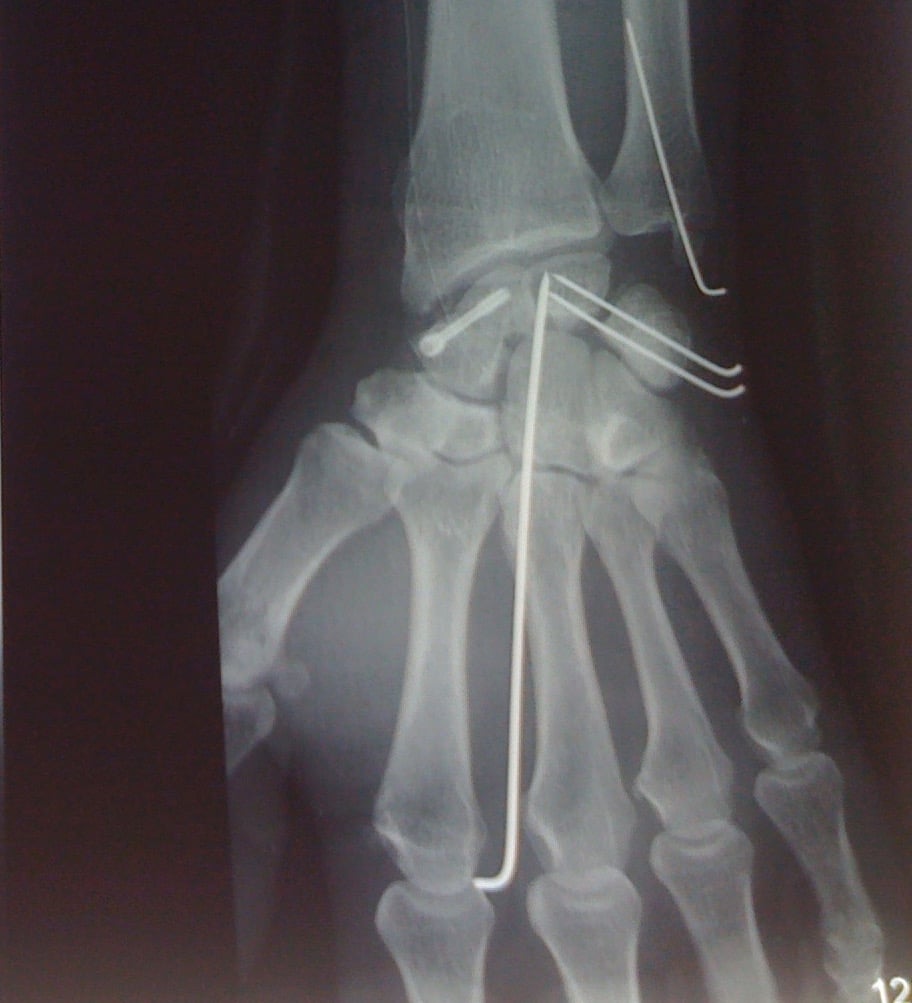

Vissage du scaphoïde

Fracture du scaphoïde

Le scaphoïde est un des os du carpe du poignet. Pièce maîtresse, véritable clef de voûte du poignet, il peut être le siège de fracture à la suite d’une chute sur la main. Cette fracture, peu douloureuse, passe parfois inaperçue ou est assimilée à une entorse et le patient ne consulte pas de spécialiste. Le diagnostic exige des clichés radiographiques à 15 jours d'intervalle, ou un scanner, qui permet plus sûrement de confirmer la fracture du scaphoïde.

L’intervention est complexe, réalisée par un spécialiste du membre supérieur, il peut s’agir d’une greffe prélevée au niveau du bassin ou d’une greffe amenée avec une artère prélevée au niveau du poignet (greffon vascularisé).